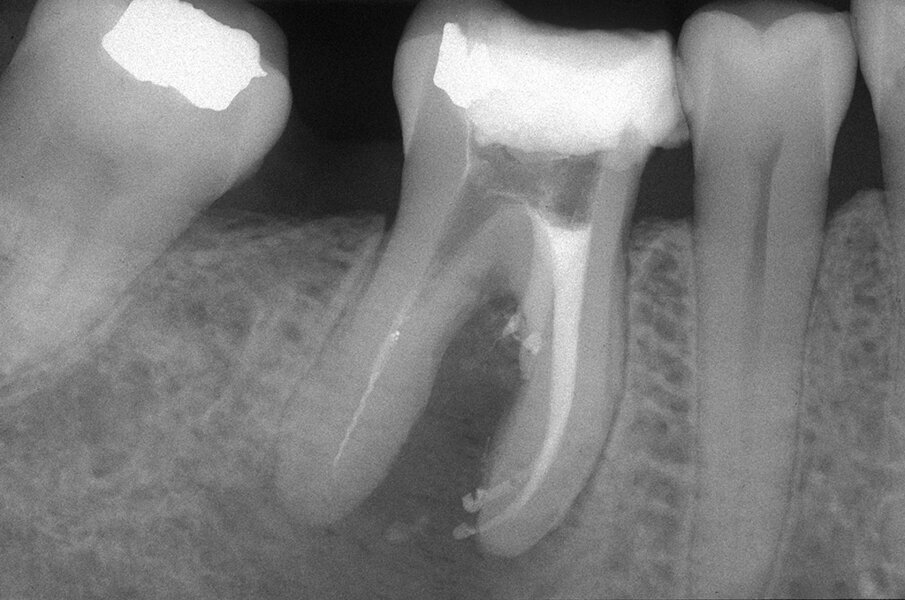

Tali perforazioni sono piuttosto frequenti a livello degli incisivi superiori, dove l’errore che più spesso viene commesso è rappresentato dall’utilizzo della fresa con eccessiva angolazione vestibolare. Perforazioni del terzo coronale possono anche accadere sul pavimento dei molari quando gli orifizi canalari vengono cercati in posti sbagliati. Tipiche sono le perforazioni nei molari superiori o inferiori, che avvengono per lo sfondamento del pavimento della camera pulpare (Figg. 3a-3i). Come conseguenza del trauma meccanico, si ha una rapida distruzione del legamento parodontale. L’osso alveolare immediatamente adiacente alla perforazione si riassorbe con conseguente perdita verticale di osso. Il processo infiammatorio quindi si estende coronalmente lungo le fibre del legamento parodontale, con distruzione del legamento, dell’osso alveolare e delle fibre gengivali sopracrestali. Come conseguenza di ciò, si ha la migrazione apicale dell’attacco epiteliale e le formazione di un grave difetto parodontale9.